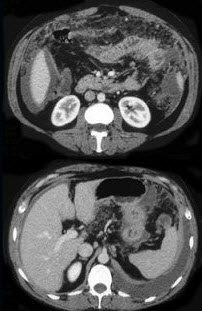

女,36岁,低热、乏力,腹胀不适1月余,结合影像检查,应考虑为( )

A:肝硬化腹水

B:结核性腹膜炎

C:腹腔转移瘤

D:心源性腹腔积液

E:急性化脓性腹膜炎